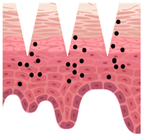

| Types of MNs | Solid MNs | Coated MNs | Dissolving MNs | Hollow MNs | Swellable MNs |

|---|---|---|---|---|---|

| Just before insertion |  |  |  |  |  |

| After application |  |  |  |  |  |

—MN loaded with active ingredients;

—MN loaded with active ingredients; —solid needle;

—solid needle; —dissolving/swellable needle;

—dissolving/swellable needle; —stratum corneum.

—stratum corneum.| Material | Characteristics | Cosmetic Benefits | 3D Printability |